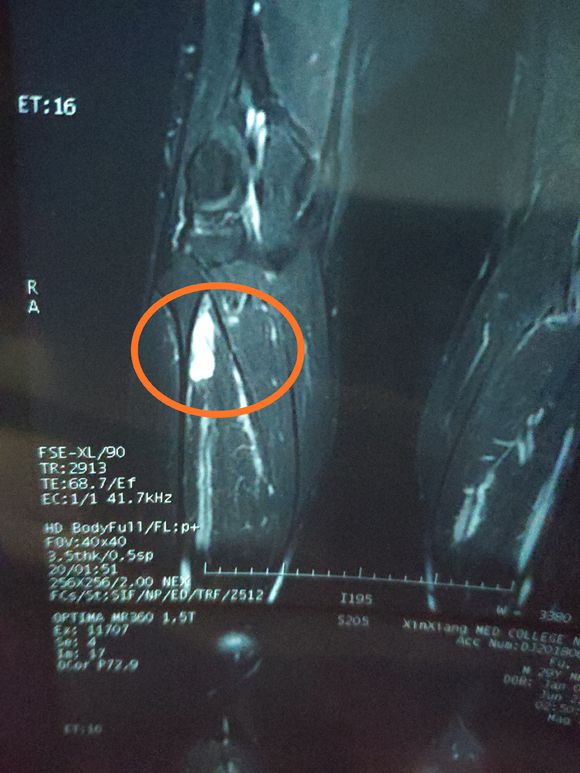

X-man 02019-01-22 患者本人十九岁,九月十号因恶性骨肉瘤在云南省肿瘤医院做了截肢手术,后发现肺上有三个结节,一个大约一厘米,两个不足一厘米,请问...